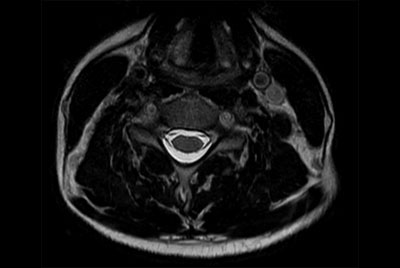

Neck stenosis